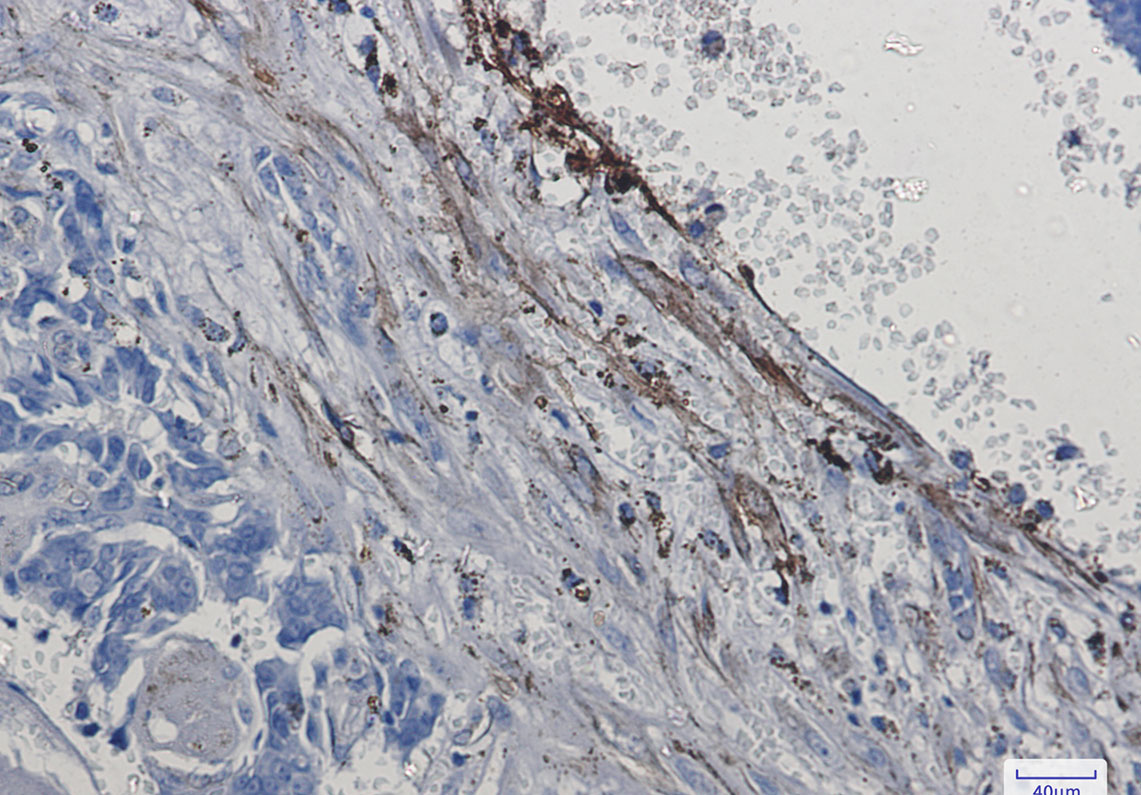

推荐稀释比 WB:1/500-1/1000;IHC:1/50-1/100;IP:1/20

应用案例

Immunohistochemistry analysis of paraffin-embedded Human breast cancer using Integrin alpha 5 antibody.High-pressure and temperature Sodium Citrate pH 6.0 was used for antigen retrieval.